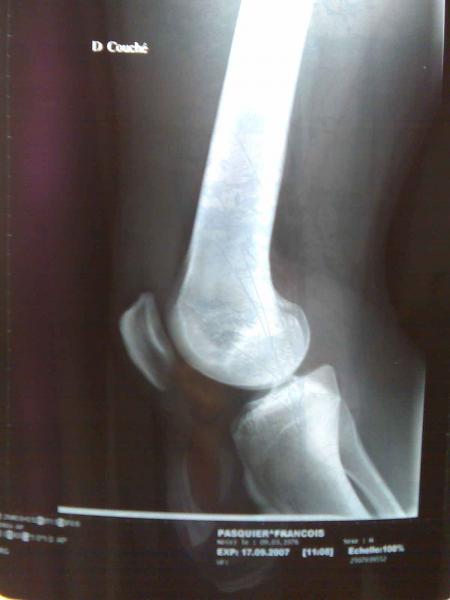

CONTRE RENDU IRM :

RUPTURE DU LIGAMENT CROISE ANTERO-EXTERNE.![]()

(le fameux.....)

FISSURATION VERTICALE DE GRADE 3 ASSOCIEE A LA POSTERIEUR DU MENISQUE.![]()

dc intervention chirurgicale en vue.......dc en gros c'est, 45MN d' operation, et pas de foot avt 4 mois a partir de la date d' operation ( si tout va bien bien sur...) et une putain de reeducation de la mort....WOUèèèèGROOOO

bon apres un pti tour a l hopital St Louis, une batterie de tests et de radios, RIEN DE CASSé, les ligaments ont l' air OK. c' est les menisques qui en ont pris un pti coup...donc IRM samedi. en attendant, attelle de la jambe pendant 2 semaines. a suivre....